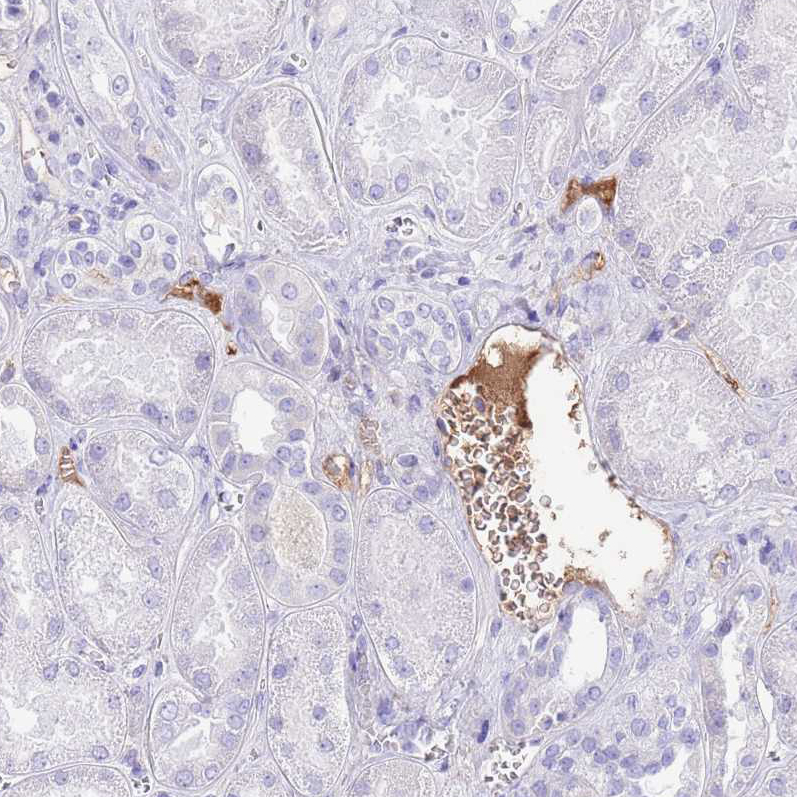

Immunohistochemical staining of human placenta shows moderate positivity in plasma.